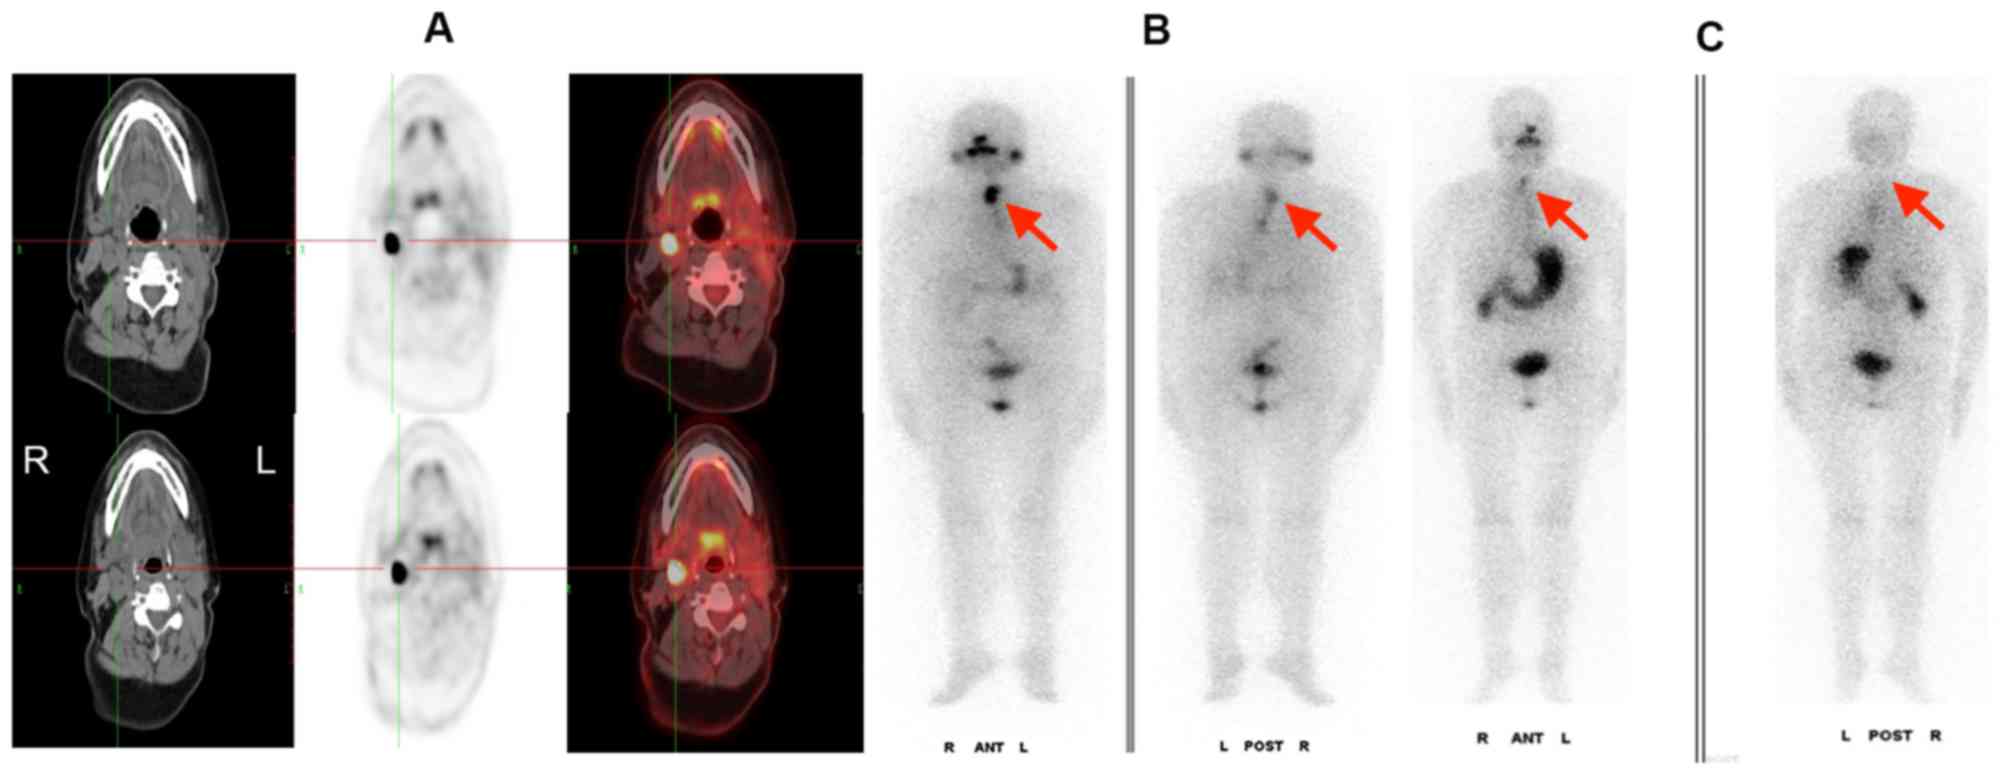

Panel Of 18 F FDG PET CT Imaging At 6 Months Follow up Of Patient 7

https://www.researchgate.net/profile/Brunolf_Lagerveld/publication/286478657/figure/download/fig6/AS:306456508289029@1450076333191/Panel-of-18-F-FDG-PET-CT-imaging-at-6-months-follow-up-of-patient-7-There-are-2-FDG-avid.png

Figure 1 18F FDG PET CT Scanning Identifying Pacing Box Infection With